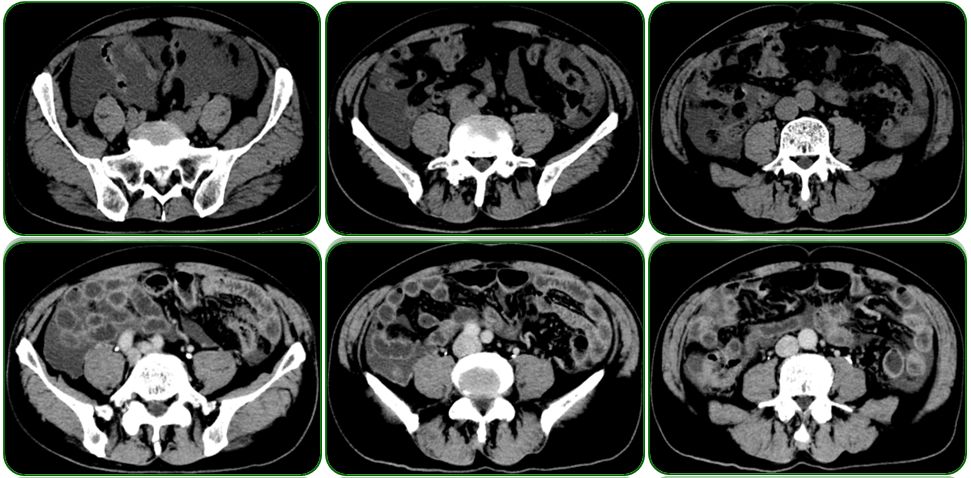

外院胃镜检查见吻合口粘膜充血水肿,残胃未见溃疡及肿物,如图1;

腹部CT提示腹盆腔中量积液,初步考虑结核可能,如图2;

肠镜检查未见明显异常,如图3;

图1 胃镜检查

图2 腹部CT检查

图3 肠镜检查